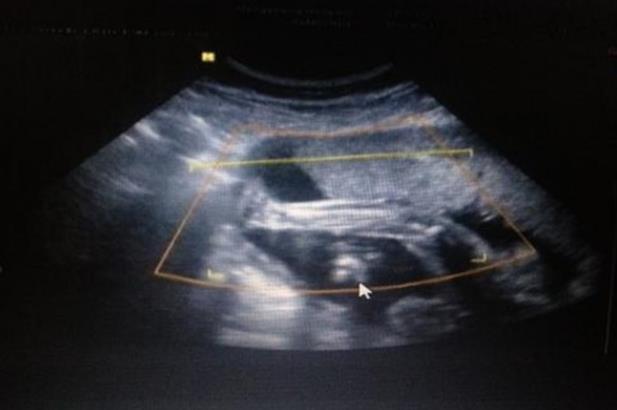

二胎宝宝,第一胎在六年前到时真的是糊里糊涂的,出血以为是来例假了,后面才发现是怀孕,没有验过孕酮,只照了两次B超,还有一次还是因为被同事说了前三个月要多注意又去照的,大宝就这么顺顺利利剖腹出来了,女宝。现在二胎多了好多流程,有可能是年龄的原因,孕酮偏低,但是雌二醇和HCG正常增长,每次验都下降,第一次75,第二次59,第三次57,第四次49.6,第五次49.8,20天内验了5次血,打针吃药不停,昨天B超有胎心胎芽的,终于放心多了,现在是用中西医结合的方法保胎。